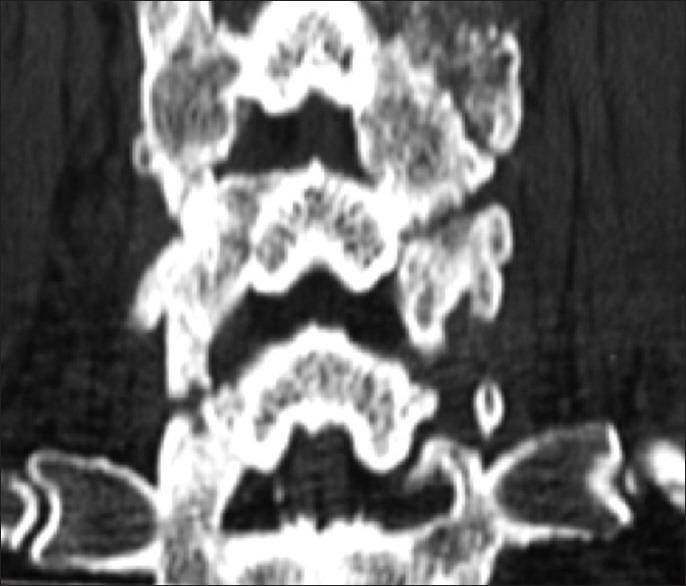

Two successive prospective cohorts of patients underwent 1-3 level laminectomies with 5-9 level posterior cervical fusions to address cervical spondylotic myelopathy (CSM) and/or ossification of the posterior longitudinal ligament (OPLL). The first cohort of 72 patients received Vitoss, while the second cohort or 20 patients received NanOss. Fusions were performed utilizing the Vertex/Rod/Eyelet System (Medtronic, Memphis, TN, USA) with braided titanium cables through the base of intact spinous processes (not lateral mass screws) cephalad and caudad to laminectomy defects. Fusion was documented by an independent neuroradiologist blinded to the study design, utilizing dynamic X-rays and two dimensional computed tomography (2D-CT) studies up to 6 months postoperatively, or until fusion or pseudarthrosis was confirmed at 1 year.

Vitoss and NanOss resulted in comparable times to fusion: 5.65 vs. 5.35 months. Dynamic X-ray and CT-documented pseudarthrosis developed in 2 of 72 Vitoss patients at one postoperative year (e.g. bone graft resorbed secondary to early deep wound infections), while none occurred in the 20 patients receiving NanOss.

连续两组前瞻性队列患者接受了1 - 3节段的椎板切除术及5 - 9节段的后路颈椎融合术,以治疗颈椎脊髓型颈椎病(CSM)和/或后纵韧带骨化症(OPLL)。第一组72例患者接受了Vitoss,而第二组20例患者接受了NanOss。融合手术采用Vertex/棒/小孔系统(美国田纳西州孟菲斯市美敦力公司),通过完整棘突基部(而非侧块螺钉)在椎板切除缺损的头侧和尾侧使用编织钛缆。由一位对研究设计不知情的独立神经放射科医生通过动态X线和术后6个月内的二维计算机断层扫描(2D - CT)研究记录融合情况,或直至术后1年确认融合或假关节形成。

Vitoss和NanOss的融合时间相当:分别为5.65个月和5.35个月。术后1年,72例接受Vitoss治疗的患者中有2例经动态X线和CT记录出现假关节形成(例如因早期深部伤口感染导致骨移植吸收),而接受NanOss治疗的20例患者中未出现假关节形成。